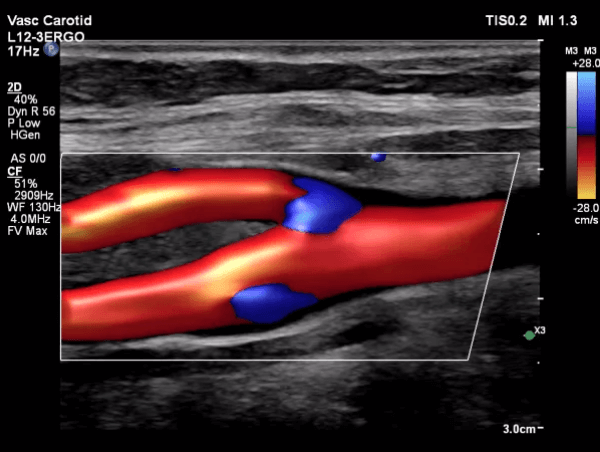

Dr. Ghalichi personally performs carotid artery ultrasounds using the state-of-the-art Philips EPIQ Elite (Netherlands) system equipped with AI tools.

• Operator-Dependent Expertise: Benefit from Dr. Ghalichi's specialized skills in conducting and interpreting the ultrasound.

• Intima-Media Thickness (IMT) Measurement: Accurate assessment of the thickness of your arterial walls.

• Radiation-Free Imaging: Safe and painless procedure with no exposure to radiation.

• Trackable Results: Monitor changes in IMT over time to evaluate the effectiveness of treatment strategies.

Carotid Artery Ultrasound Image 1 Carotid Artery Ultrasound Image 2